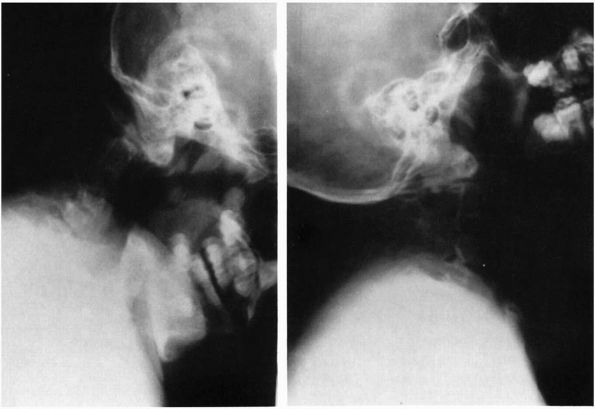

![]() |

FIGURE 11-5. Cervical myelogram demonstrating herniated disc with left C5-C6 nerve root compression.

FIGURE 11-6. (A)

A sagittal T2-weighted MRI scan of the cervical spine demonstrates chronic disc protrusions at C3-C4 and C4-C5 along with infolding of the ligamentum flavum at those same levels. This is typical of cervical spondylosis and the resultant cord compression has created “gliosis” changes within the cord as illustrated by the increased signal intensity within the cord at the C3-C4 disc level. (B) The corresponding T2 axial images at C3-C4 in the same patient further defines the degree of cord deformity from the compression. |

FIGURE 11-7. Normal cervical diskograms: (A) lateral view; (B) AP view. (C) “Mushroom” diskogram. (Dye around the posterior osteophyte beneath the posterior longitudinal ligament.) (D) Massive posterior disc rupture. (E) and (F) Examples of unilateral disc rupture.

defining root sleeve pathology (Figure 11-5).

It must be remembered that myelography does not define the most lateral

component of the neuroforaminal encroachment because the subarachnoid

space does not extend out to the full extent of the neuroforamen along

with the nerve roots. Myelography with flexion and extension views can

demonstrate dynamic cord compression related to bulging of the

posterior longitudinal ligament and ligamentum flavum, or to spinal

instability.

the cervical spine. Although CT scanning is still better at delineating

bone from soft tissue, the MRI is far superior in defining soft tissue

anatomy (Figure 11-6). The disc material and

nerve anatomy can be seen as well as demonstrating pathophysiolocal

effects such as “gliosis” associated with chronic spinal cord

compression. Be careful in assessing the amount of canal compromise on

T2-weighted image because the degree of stenosis can be overestimated.

Under those circumstances a CT or myelogram can be a complimentary

study. Infections, hematomas, and tumors are also much better

visualized by MRI.

injecting it with a radiopaque substance, thus obtaining a cervical

diskogram (Figure 11-7). Distinctive diskogram

determinations are dynamic tension on injection, the actual diskogram

appearance on radiograph, and the reproduction of pain response. In the

cervical spine, reproduction of clinical symptoms with injection is

more important than the actual descriptive interpretation of the

diskogram. Diskography is not a routine diagnostic procedure. It is

important, however, to recognize that abnormal diskograms and pain

produced locally and at a distance by injecting can be demonstrated in

some asymptomatic people. The percentage of false-positive examinations

increases with advanced age. The procedure itself, therefore, is not

infallible proof of an abnormal symptom.